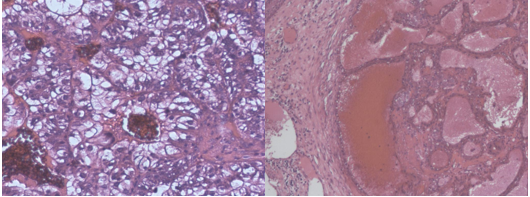

Se envía el tejido para estudio histopatológico y se confirma una neoplasia metastásica carcinomatosa, con presencia de células claras que alternan con células de citoplasma granular y muy rica vascularización. (Figs. 8 y 9).